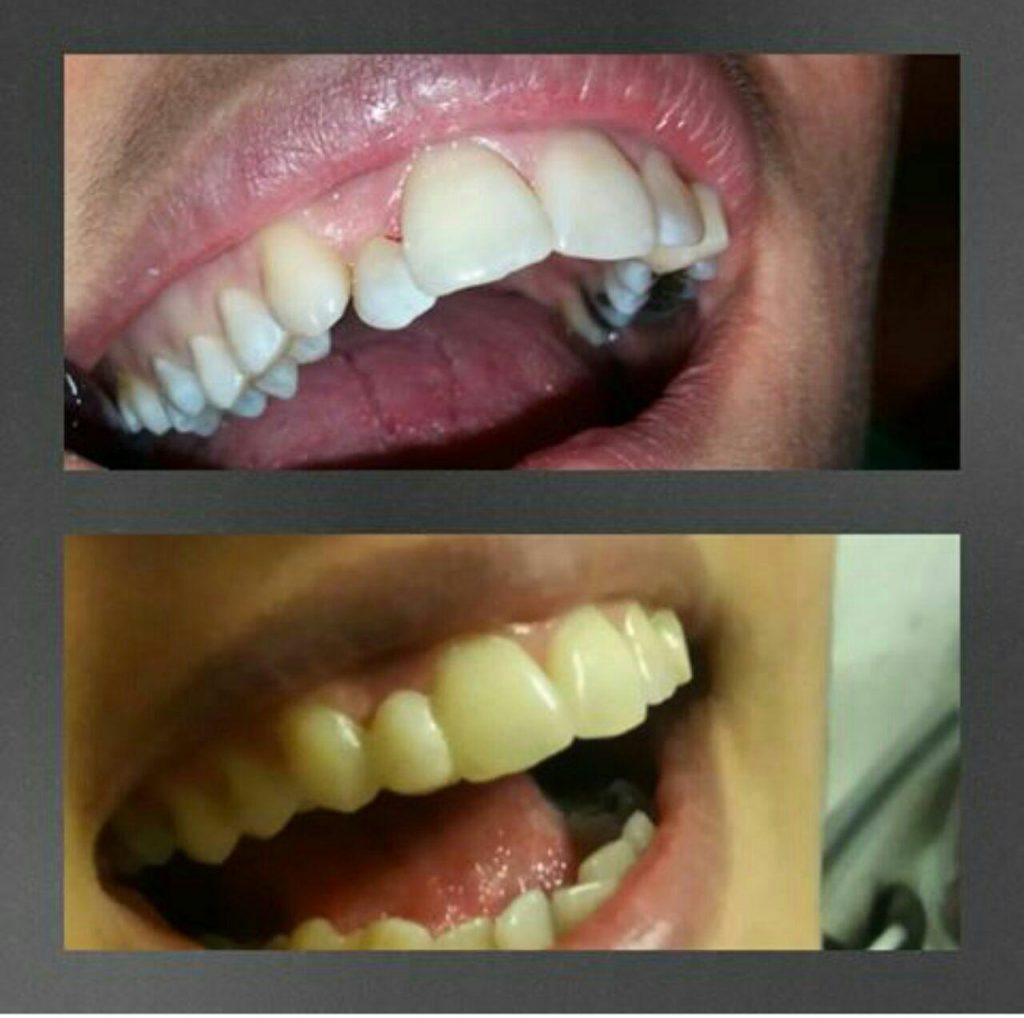

آیا میتوان بلافاصله بعد از برداشتن دندانها، بریج را مستقیما نصب کرد؟

پاسخ به این سؤال منفی است. ممکن است بعد از کشیدن دندانها حداقل ۶ ماه زمان ببرد تا لثهها بهدرستی ترمیم شوند و فک و لثه موقعیت طبیعی خود را به دست آورند. ازاینرو بهتر است تا ترمیم لثهها و نصب بریج یکیک پل دائمی است، در این مدتزمان از دندانهای مصنوعی یا پروتز دندانی موقت استفاده شود.